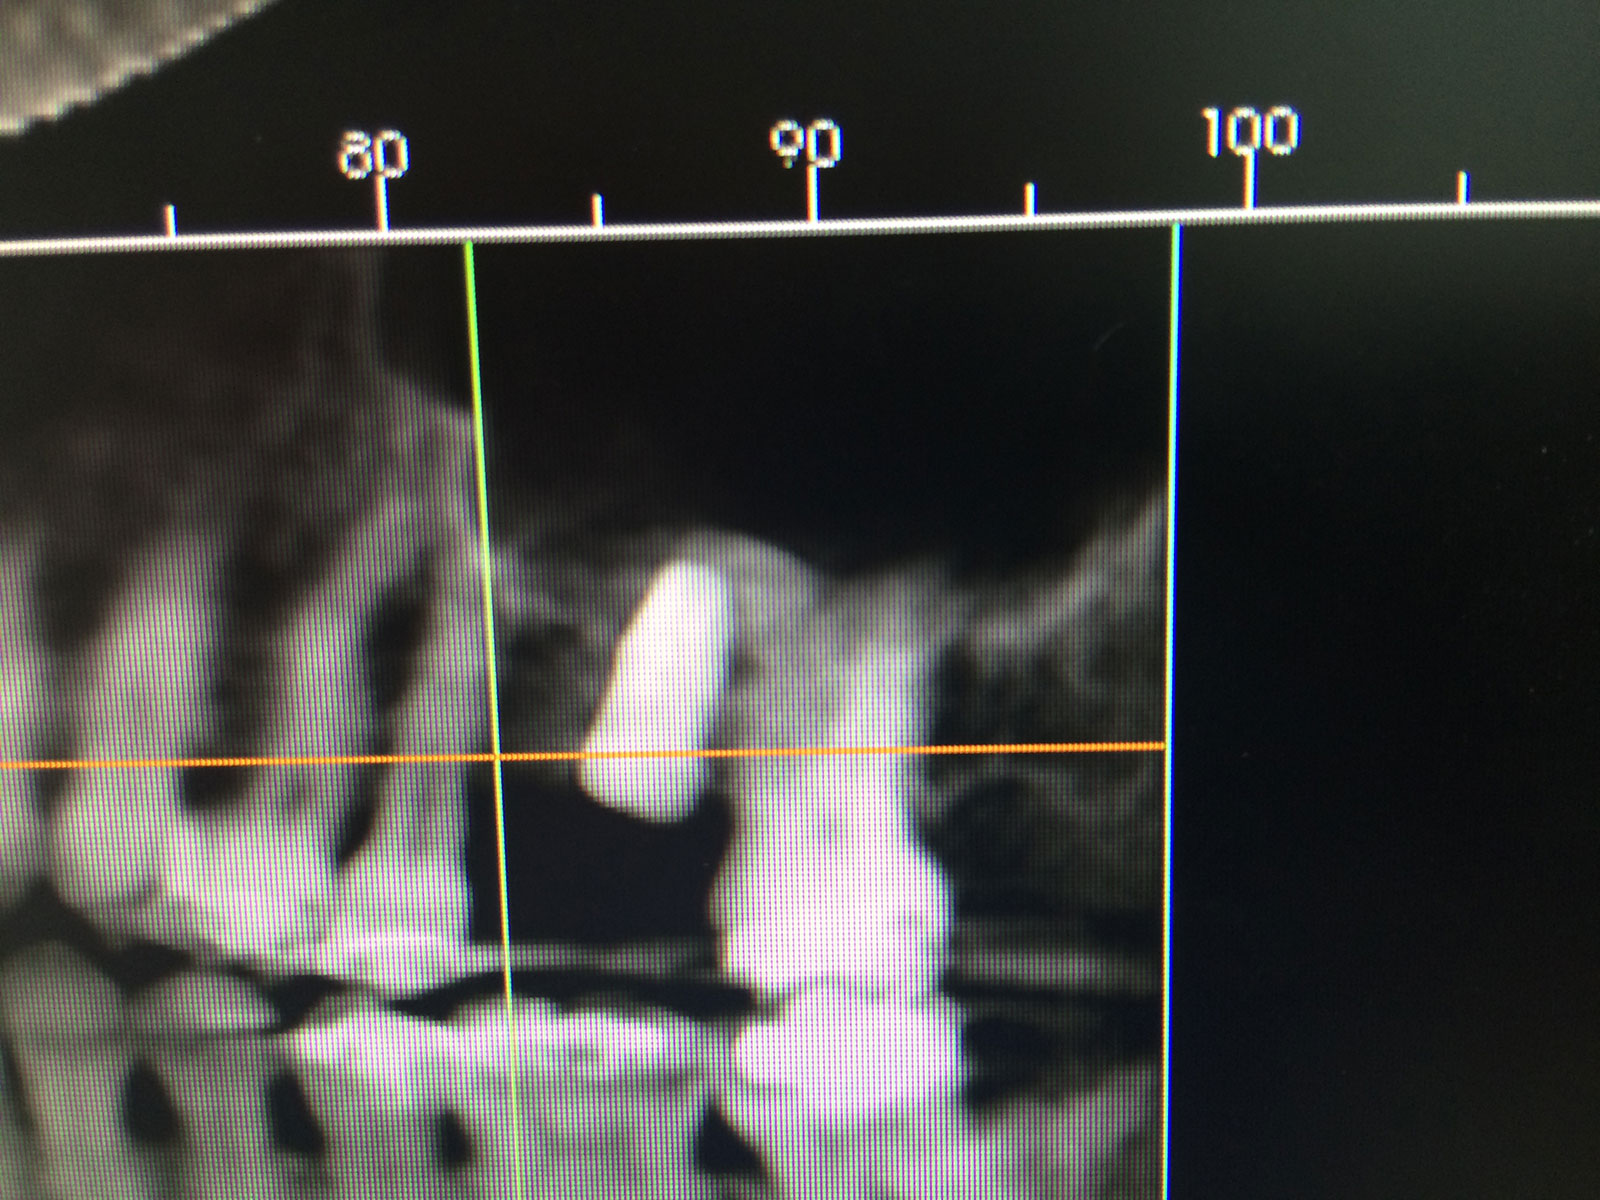

Sinus Grafting Procedures

A sinus grafting procedure, also known as a sinus augmentation, is for patients who have insufficient natural bone in the areas where dental implants are needed. They are long lasting, strong and sturdy, and fit and function like natural teeth. The procedure involves adding bone, either your own natural bone from another part of the body, from a donor or made of processed or synthetic bone material, and placing it below the sinus so that the implants can be placed. After the bone has healed and developed, usually around four to 12 months, the dental implants can be placed.